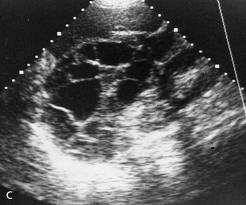

We carry the latest advances in technology to help diagnose the toughest of cases. Our imaging capabilities include digital radiography, contrast radiology, and digital ultra-sound equipment. We also have a fully equipped laboratory for running same day diagnostic blood counts and serum chemistries. Certified microscopic training allows for screening and detection of cancerous lesions and blood borne parasites that are not normally offered at most clinics.